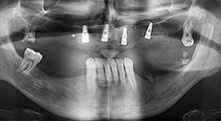

Bratu: We routinely use the instruments for harvesting bone blocks and splitting alveolar ridges. We also use the Piezomed B6/B7 for osteotomy of impacted teeth and removing failed implants. All indications that require deep, clean cuts.

Bratu: I consider piezo surgery a great leap forward in oral surgery. The technique makes bone preparation safer and easier. Little bone is lost, for example in extractions. This is very important in the aesthetic zone, particularly if immediate implantation is planned. Piezo surgery is also safer for soft tissue: injuries to membranes in the sinus are basically history, as are nerve injuries when bone blocks are being harvested. Data indicating reduced postoperative swelling and pain are also available. Piezo surgery is also ideal for preparation of sinus septa. And last but not least, our patients benefit from the atraumatic nature of this technology.